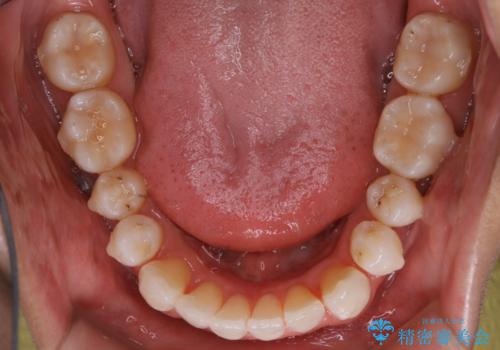

【非抜歯】八重歯を治す マウスピース矯正

- 前歯のガタつきの治療を主訴にご来院されました。

目立たない装置をとのご要望があったため、検査結果をふまえてインビザラインでの非抜歯矯正を行うこととなりました。

非抜歯での治療

抜歯をせずに歯のガタつきを治すためのスペースを作るために

①歯の遠心移動

②歯列弓の拡大

③IPR(歯を少し小さく削る)

この3つの方法を複合的に組み合わせて治療を行いました。

抜歯をせずとも笑った時の歯の見え方が劇的に変化していることが分かります。